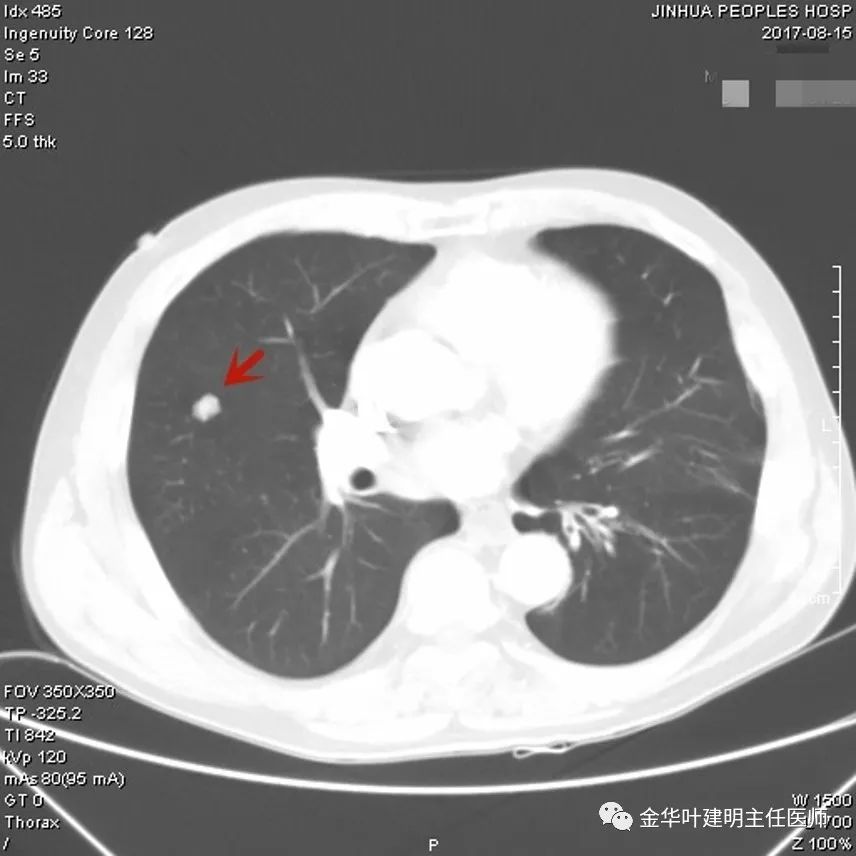

上图示胶原结节。我的理解是较慢性炎更向纤维瘢痕钙化发展,但仍未达钙化程度的一种状态(我不知道病理是不是这样)。该病灶表现为小而密度高的结节,边缘清晰,邻近胸膜却不牵拉,没有收缩力。